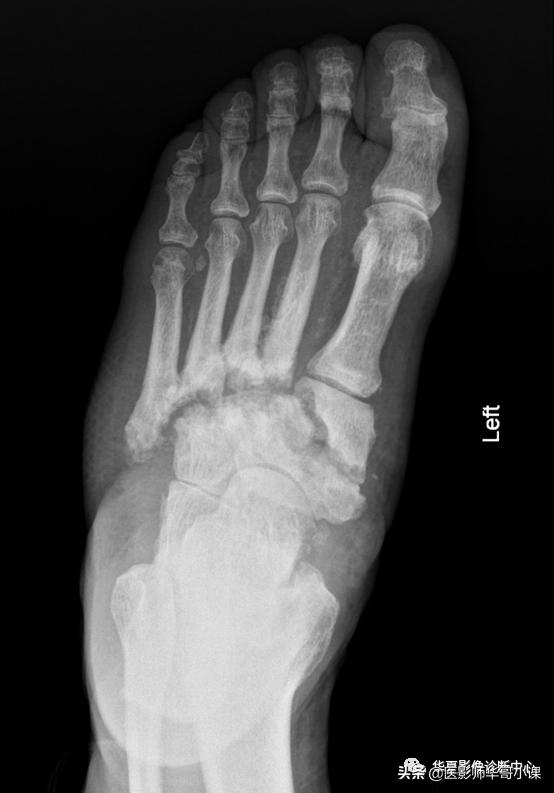

- 足和踝

- 病因:长期难以控制的糖尿病、梅毒

- 软组织肿胀、发热、红斑

- 部位:通常由中足开始

- 血管钙化

- 半脱位(起始于第2跖跗关节)

- 跟骨后结节撕脱性骨折

- 第2趾骨头软骨下骨折

- 距(骨)舟(骨)的移位伴中足骨病变

- 鉴别诊断:骨髓炎、脓毒性关节炎(通常局限于一个关节)

左足跖跗关节神经性骨关节病,第2~5跖跗关节及跗舟关节骨质破坏,破坏区周围可见碎骨片,跖骨间可见血管钙化。左足第1~2跖骨基底部及对应跗骨间可见Lisfranc脱位。